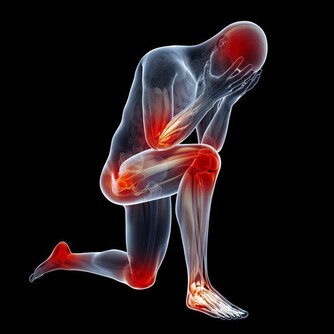

2、下肢動脈閉塞患者

下肢動脈閉塞的表現雖然是下肢缺血,但是熱水泡腳並不能擴張閉塞的血管。當然,通暢動脈的擴張,只是增加了正常組織的血流,而缺血組織可能因為“盜血”現象,更加缺血。相關數據說明,周圍溫度的升高,能夠添加安排的耗氧量,加重缺血。